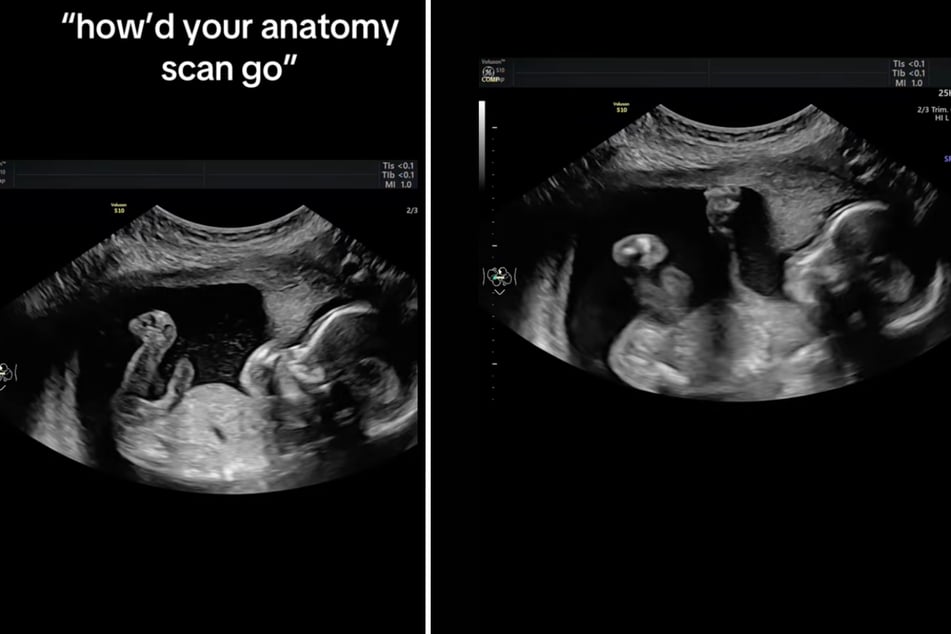

Mara McCoy war zu diesem Zeitpunkt in der 20. Schwangerschaftswoche und hatte damit sozusagen die Halbzeit bis zur Geburt eingeläutet. Mit ihrem Ehemann Terrance war sie bei einer Routine-Untersuchung, wo auch ein Ultraschall vorgenommen wurde.

Was dann aber passierte war zumindest für Mutter Mara sowohl sichtbar als auch spürbar: "Babygirl hat beschlossen, mich heute anzugreifen", schreibt die US-Amerikanerin zu ihrem Video auf TikTok.

Im Clip sieht man, wie das ungeborene Kind sich während der Ultraschall-Aufnahme zunächst ganz ruhig verhält, bis es plötzlich mit der Faust ausholt und von Innen gegen die Bauchdecke seiner Mutter schlägt.

"Das ist kein AI", fügt die Schwangere hinzu, um ihren Zuschauern zu versichern: Dies ist wirklich passiert!

Gegenüber PEOPLE erklärt Mara weiter: "Alle im Raum haben gelacht, als sie mich geschlagen hat." Ihr Clip wurde auf TikTok schon fast 3 Millionen Mal angeklickt.

"Das Video zeigt mir, wie frech sie schon ist!", meint die werdende Mutter amüsiert. "Sie könnte die nächste Ronda Rousey sein." Rousey ist eine 38-jährige, US-amerikanische Wrestlerin, Judoka und Mixed-Martial-Arts-Kämpferin.